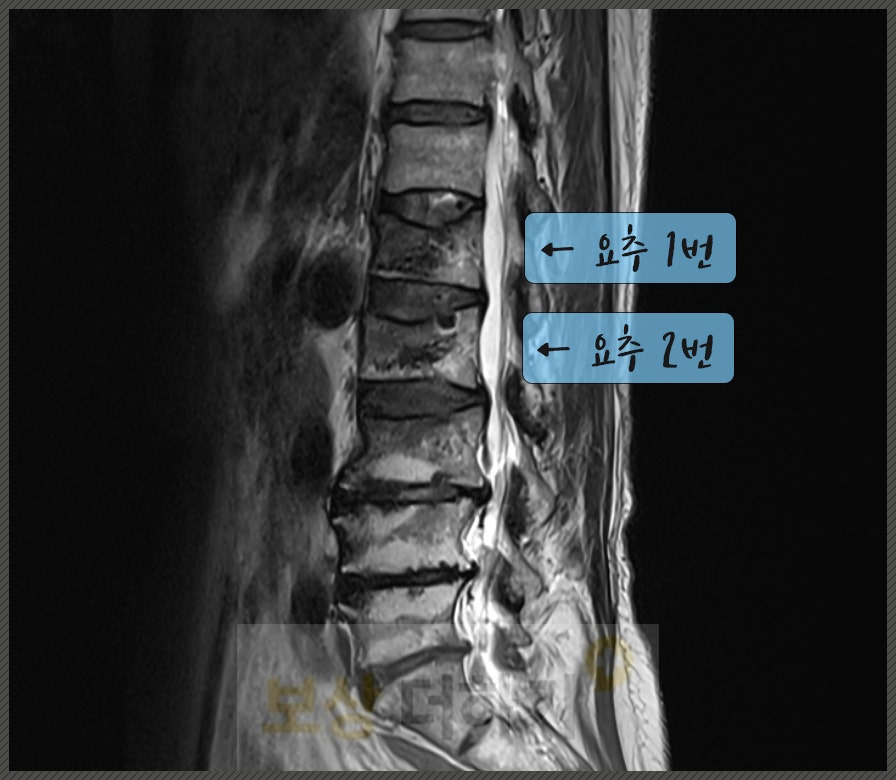

엑스레이 및 MRI 검사를 했고 허리 뼈인 요추 1번, 2번 골절이 진단됐습니다. 정확히 표현하면 압박 골절로, 넘어지실 때 충격을 크게 받으면서 척추체가 찌그러지고 눌린 것입니다.

골다공증 환자 [경피적 척추체 성형술] 골시멘트술 시행 요추 골절은 뼈 안쪽에서 미세하게 계속 무너지고 자극되면서 통증을 유발합니다. 이때 골시멘트를 주입하게 되면 뼈가 안정화되면서 통증이 감소할 수 있죠. 또한 사례자분처럼 골다공증으로 인해 뼈가 약해진 상태에서는 척추체가 계속 찌그러질 위험이 높아요. → 통증 감소, 축가적 붕괴를 막기 위해 경피적 척추체 성형술을 시행 받으셨습니다.

사례자 김 00 님은 해외여행 전 가입해 놓은 여행자 보험에 상해 후유장해 담보가 있었습니다. 「보상 더하기」로 연락을 주셨기에 영상 자료와 관련 약관 등을 검토한 결과, 전문가 개입 시 훨씬 큰 보상이 가능하겠다고 판단되었습니다. 따라서 이 사건을 수임하여 청구 전부터 실제 지급까지 전반적인 도움을 드렸습니다. 장해진단서 발급 지원 회사의 불리한 주장에 논리적인 반박 허리 (요추 1번, 2번) 골절로 인한 척추체 압박률, 기형 각도에 따라서 장해 지급률과 보상액이 달라지기 때문에 공신력 있는 의료기관에서 보다 명확한 소견을 받을 수 있도록 지원했습니다. 또한 보험회사의 불리한 주장에도 (지급률 · 장해 기간 · 기왕증 기여도) 논리적인 반박 및 추가 입증 자료를 제출, 그 결과 만족스러운 답변을 이끌어낼 수 있었습니다. → 후유장해 보험금 3,600만 원